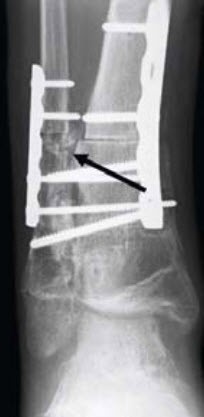

Im Gegensatz zu früheren Vermutungen ist die bösartige Entartung bei der multiplen kartilaginären Exostosenerkrankung sehr gering und liegt laut Literatur bei ca. 0.9 bis 5 Prozent. Im Verdachtsfall wird vor der operativen Behandlung eine MRI-Untersuchung empfohlen. Abb. 7–9 zeigen eine sekundäre Deformierung des oberen Sprunggelenks. Die weissen Pfeile zeigen den sekundären Aussenknöchelhochstand und die sekundäre Diastase von Innenknöchel und Sprungbein. Die Behandlung erfolgte durch Resektion der Exostose und Verlängerung des Wadenbeins unter Beckenkamminterposition und Plattenfixation (schwarzer Pfeil) sowie zeitgleicher supramalleolärer Derotationsosteotomie mit Platte. Das Ausheilungsbild am Ende des Wachstums zeigt ein wiederhergestelltes korrektes Alignement des Sprunggelenks.